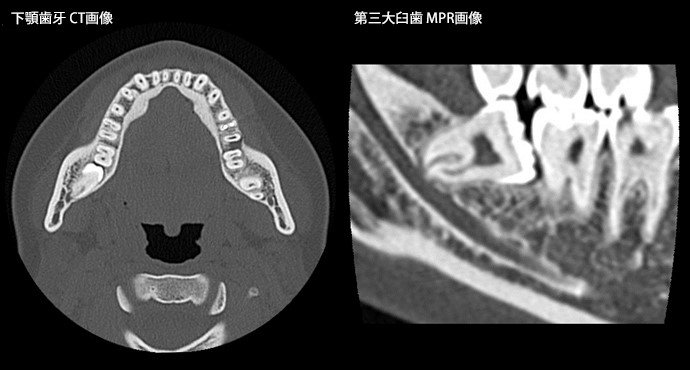

64列の強みを生かし、短時間での撮影を行うことで患者さんの負担を軽減し、耳の疾患に対しては0.5m撮影にて、微細な構造を描出します。また、被曝低減フィルターと逐次近似再構成法により、小児でも極低線量ながら、診断に十分な画像を提供します。

歯科領域 多断面再構成(MPR)